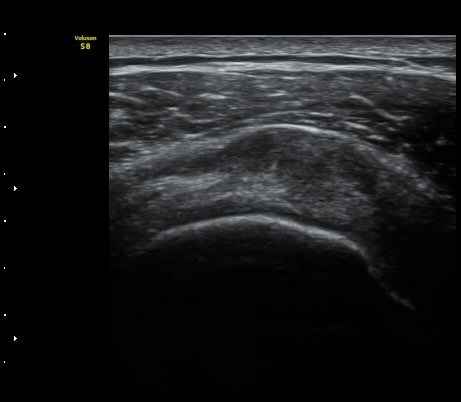

À̵ιڱ٠Ⱦ´Ü¸é°Ë»ç¿¡¼­ Á¤¸Æ³¶ÀÇ ºÎÁ¾ÀÌ °üÂûµÊ(±×¸² 1).